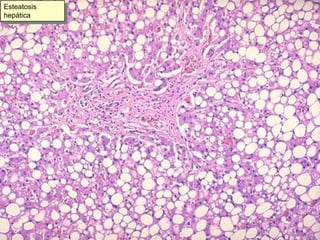

Este documento resume diferentes tipos de necrosis y otros procesos patológicos encontrados en anatomía patológica general. Describe necrosis coagulativa como infartos de miocardio y riñón, necrosis licuefactiva como infartos cerebrales, y otros tipos como necrosis grasa pancreática y necrosis caseosa en tuberculosis pulmonar. También cubre procesos como apoptosis, atrofia, hipertrofia, hiperplasia, metaplasia, displasia, y acumulaciones de sustancias como hemosiderina, amiloide y calcificaciones.